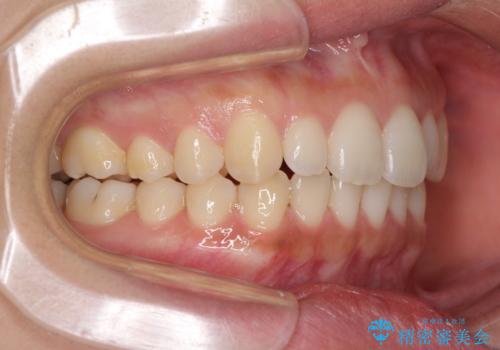

海外勤務中でも矯正治療 インビザラインによる軽度叢生改善

- 前歯のデコボコを気にして来院された患者様です。

治療期間中に海外勤務になる可能性が高いことが分かっていましたが、矯正治療を始めたいとのことでしたので、インビザラインを用いて治療することとしました。

通常であれば半年から10ヶ月程度で終了する歯並びでしたが、海外に長期出張することになったため、1年10ヶ月の期間を要しました。

出張に行かれてしまうと追加のマウスピースを発注できないため、マウスピースの交換頻度を低くし、一時帰国のタイミングに合わせていくことで、スムーズに進めて行くことができました。